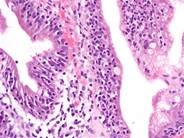

A 70-year-old Hispanic woman with history of coronary arterial disease presented with dull abdominal pain and weight loss for ∼2 weeks. A computed tomography scan of the abdomen revealed a large mass occupying the proximal jejunum. The patient had no history of celiac disease or malabsorption. She underwent surgical resection. Grossly, the tumor measured 10 cm in length and had a multinodular appearance with surface ulceration and a soft “fish flesh,” yellow-white, homogenous cut surface (panel A). Microscopically, the tumor consisted of monomorphic small lymphocytes (panel B) positive for cytoplasmic CD3, CD8, CD56, and T-cell receptor γ (TCR-γ), and negative for CD4, CD20, CD30, and TCR-β.Enteropathy-associated T-cell lymphoma (EATL) is a lymphoma of intestinal intraepithelial T lymphocytes. The World Health Organization divided EATL into 2 variants: a classical form (type I), which comprises 80% to 90% of cases, and a type II or monomorphic variant, which comprises 10% to 20% of EATL cases. The classical form consists of large pleomorphic lymphoma cells which are usually CD3 +, CD5 −, CD7 +, CD8 −/+, CD4 −, CD56 −, TCRβ +/−. Type II is composed of small round monomorphic cells. The tumor cells in type II are CD3 +, CD4 −, CD8 +, CD56 +, and TCRβ +. Type I is mostly associated with celiac disease. The monomorphic variant may also be preceded by celiac disease but it has not been well characterized.